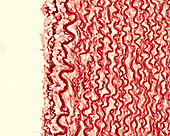

13613450 - Elastic lamellae in aorta, light micrograph

13613436 - Elastic lamellae in aorta, light micrograph

13613447 - Elastic lamellae in aorta, light micrograph

13613449 - Elastic lamellae in aorta, light micrograph

13613433 - Elastic lamellae in human aorta, light micrograph

12360842 - Elastic lamellae, light micrograph